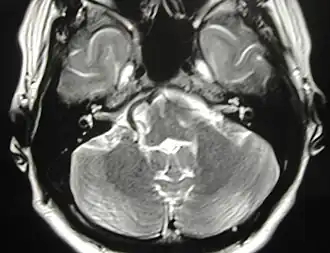

Аксиальная МР-томограмма. Конфликт артериального сосуда с правым лицевым нервом. Клиническая картина: правосторонний гемифациальный спазм.

Основным этиопатогенетическим фактором развития синдромов микроваскулярной компрессии краниальных нервов является механическое воздействие пульсирующего сосуда на ствол нерва с последующим распространением патологической импульсации и развитием пароксизмальной функциональной активности соответствующего краниального нерва (парокзимальная лицевая боль — при воздействии на тройничный нерв, пароксизмы сокращения мышц лица — при воздействии на лицевой нерв). Согласно литературным данным, полученным на больших сериях наблюдений, чаще всего наблюдается конфликт нерва с артериальным сосудом (передней нижней мозжечковой артерией, задней нижней мозжечковой артерией, позвоночной артерией, базилярной артерией), редко отмечается конфликт нерва с венозным сосудом[15]. С развитием методов нейровизуализации, внедрением в широкую практику операционной микроскопии и, как следствие, улучшением техники хирургических вмешательств, компрессия лицевого нерва эктазированными сосудами стала считаться основной причиной гемифациального спазма, а концепция нейроваскулярного конфликта в генезе синдромов микроваскулярной компрессии стала приобретать все большее количество сторонников[16],[17],[18],[19]. Согласно постулатам P.Jannetta, сдавление нерва происходит в зоне входа\выхода корешка нерва (REZ — root exit\entry zone). В зоне выхода корешка более тонкий центральный глиальный миелин переходит в толстый, периферический «шванновский миелин», впервые эта анатомическая особенность описана H.Obersteiner и E.Redlich в 1894 г. (зона Obersteiner-Redlich). Контакт сосудов с зоной выхода корешка вестибулярного нерва приводит к появлению в клинической картине жалоб на головокружение, а при контакте сосудов с зоной выхода корешка кохлеарного нерва появляются жалобы на снижение слуха и шум в ушах. Возможна сочетанная компрессия корешков V и VII нервов, в этом случае гемиспазм будет сопровождаться лицевой болью (сочетание невралгии тройничного нерва и гемифациального спазма).

В 90-е гг. с появлением высокопольных МР-томографов с высокой разрешающей способностью и последующей разработкой специального программного обеспечения (программ трехмерной реконструкции) возможности метода значительно расширились. Появилась возможность неинвазивной визуализации нейроваскулярного конфликта.

На современном этапе развития МРТ в большинстве случаев позволяет выявить причину гемифациального спазма (опухоль, аневризма, сосудистая мальформация в области мосто-мозжечкового угла, очаг демиелинизации, очаг лакунарного инфаркта) и визуализировать нейроваскулярный конфликт, то есть дифференцировать вторичный и первичный спазм.